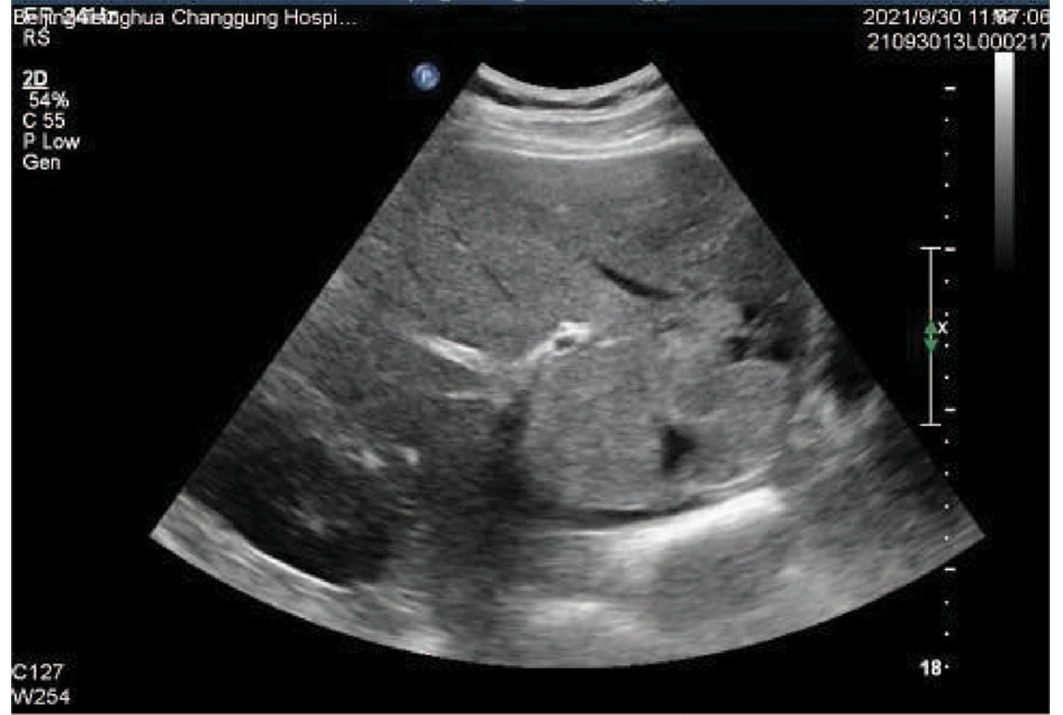

Congenital left hepatic deficiency with hepatocellular carcinoma: A case report

Hailin WANG, Jingdong LI, Guo WU

2023, 39(6): 1408-1410. DOI: 10.3969/j.issn.1001-5256.2023.06.023

Abstract(853) HTML (199) PDF (2003KB)(65)